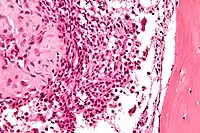

Histological Findings

Chondroid differentiation is a common feature of chondroblastoma.[10][12][13] A typical histological appearance consists of a combination of oval mononuclear and multi-nucleated osteoclast-type giant cells.[10][7][12] However this is not a prerequisite for diagnosis, as cells with epithelioid characteristics have been observed in lesions of the skull and facial bones.[12] A "chicken-wire" appearance is characteristic of chondroblastoma cells and is the result of dystrophic calcification that may surround individual cells.[10][14] Although, calcification may not be present and is not a prerequisite for diagnosis.[10][7][12] Mitotic figures can be observed in chondroblastoma tissue but are not considered atypical in nature, and therefore, should not be viewed as a sign of a more serious pathology.[10][12] There is no correlation between mitotic activity and location of the lesion.[12] Furthermore, the presence of atypical cells is rare and is not associated with malignant chondroblastoma.[10][13] There are no discernible histological differences observed when comparing the aggressive form of chondroblastoma that can cause recurrence or metastases with its less aggressive, benign, counterpart.